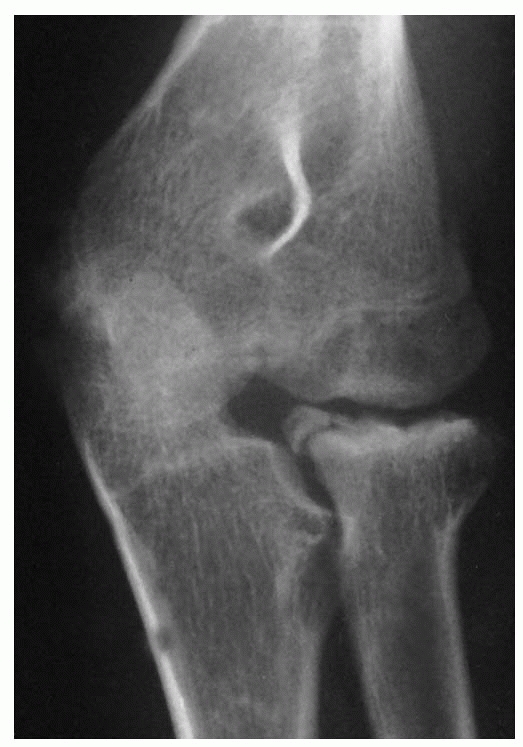

In the first two types, the fracture line involves the physis. Type A

represents either a Salter-Harris type I or II physeal injury. In a

Salter-Harris type II injury, the metaphyseal fragment is triangular

and lies on the compression side. In type B fractures, the fracture

line courses vertically through the metaphysis, physis, and epiphysis

to produce

a Salter-Harris type IV fracture pattern (see Fig. 11-11).

This is the only fracture type that involves the articular surface of

the radial head. In type C fractures, the fracture line lies completely

within the metaphysis (Fig. 11-12), and the

fracture can be transverse or oblique. Type B fractures are rare. The

incidences of types A and C fractures are approximately equal.103